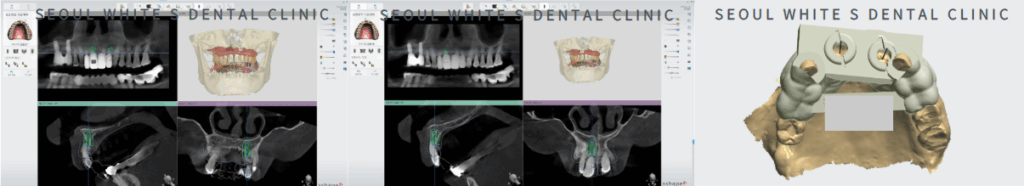

미리 제작한 가이드 홀(Hole)에 맞춰서 절개 없이, 안정적으로 식립했습니다! 4개의 치아이기 때문에 잘 지지할 수 있는 위치를 분석한 자리에 식립을 해드렸습니다.

식립할 위치로 모의 시.술을 진행하고, 자체기공소와의 협업을 통해 신속하게 가이드를 제작하였습니다.